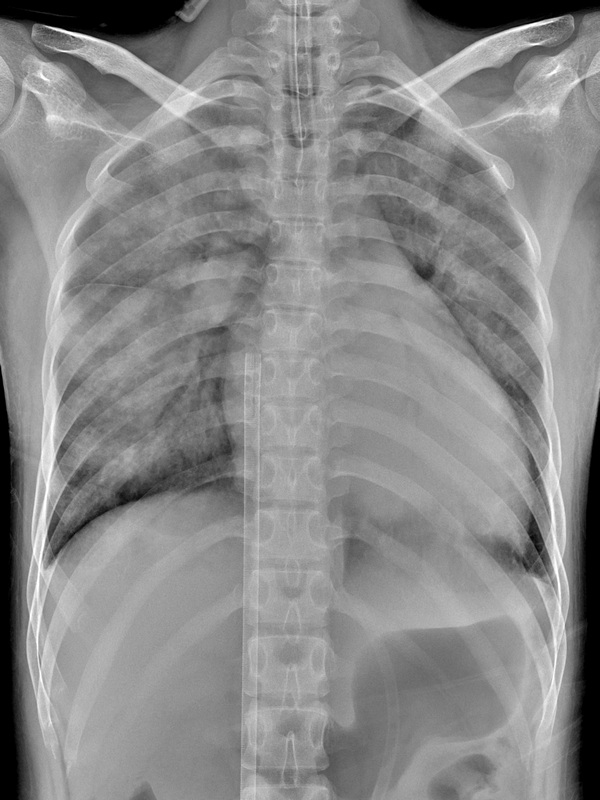

圖:鄭小姐裝上葉克膜六小時後,胸腔X光影像中肺部幾乎呈白色,肺水腫嚴重且心臟明顯擴大。